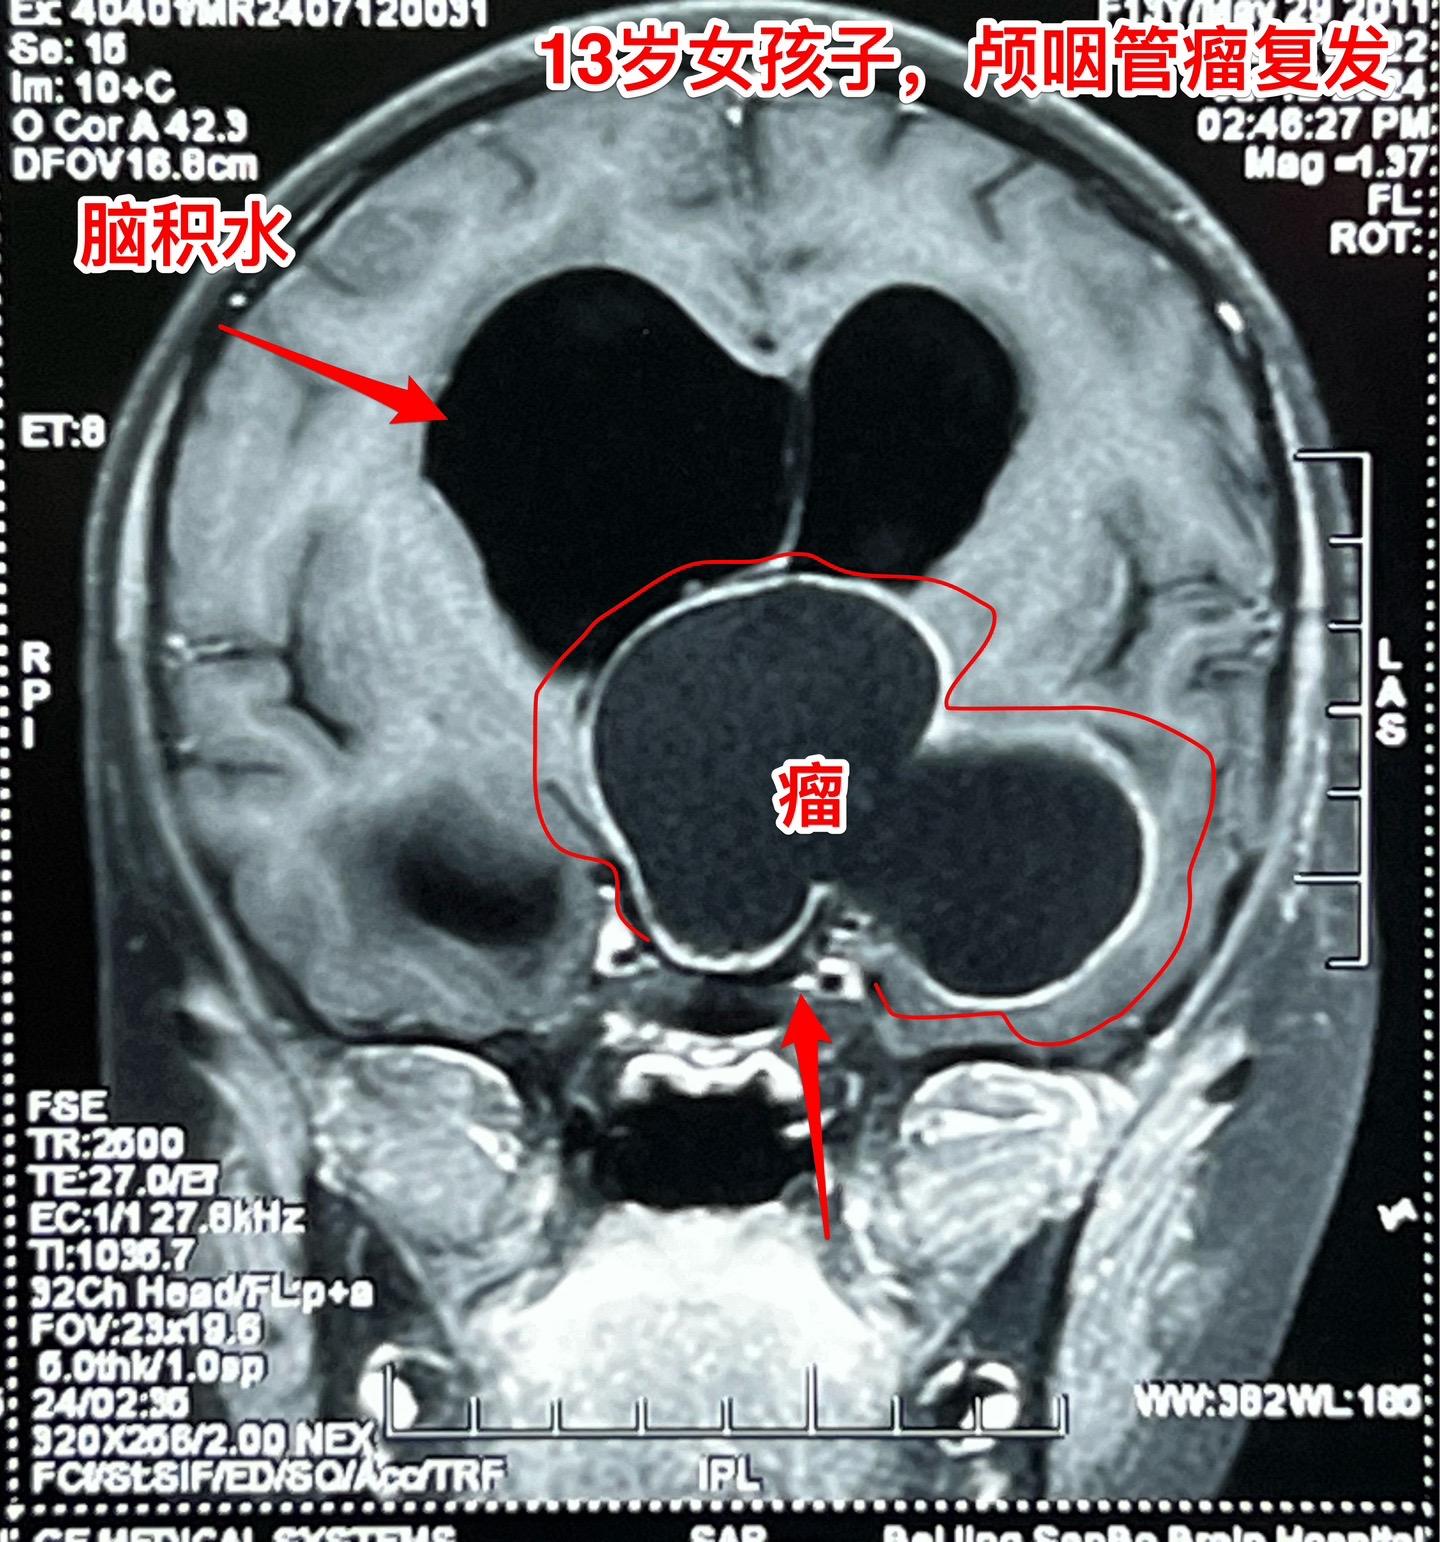

复发的巨大颅咽管瘤,难度很大。13岁四川女孩子,2022年6月在外院行开颅手术切除颅咽管瘤。半年后颅咽管瘤复发,家长采用中药治疗。中药控制颅咽管瘤的效果也不理想,肿瘤还在继续生长。 复发肿瘤体积越来越大,患儿曾经出现过头痛、呕吐、多睡症状。经过补充糖皮质激素后症状有好转。额部骨头逐渐出现隆起,见图4、5。 2024年7月16日作了开颅手术,将颅咽管瘤完全切除。肿瘤体积大,压迫脑干,而且与周围的血管粘连紧密,手术过程很艰难,最终获得完全切除。 手术后患儿很虚弱